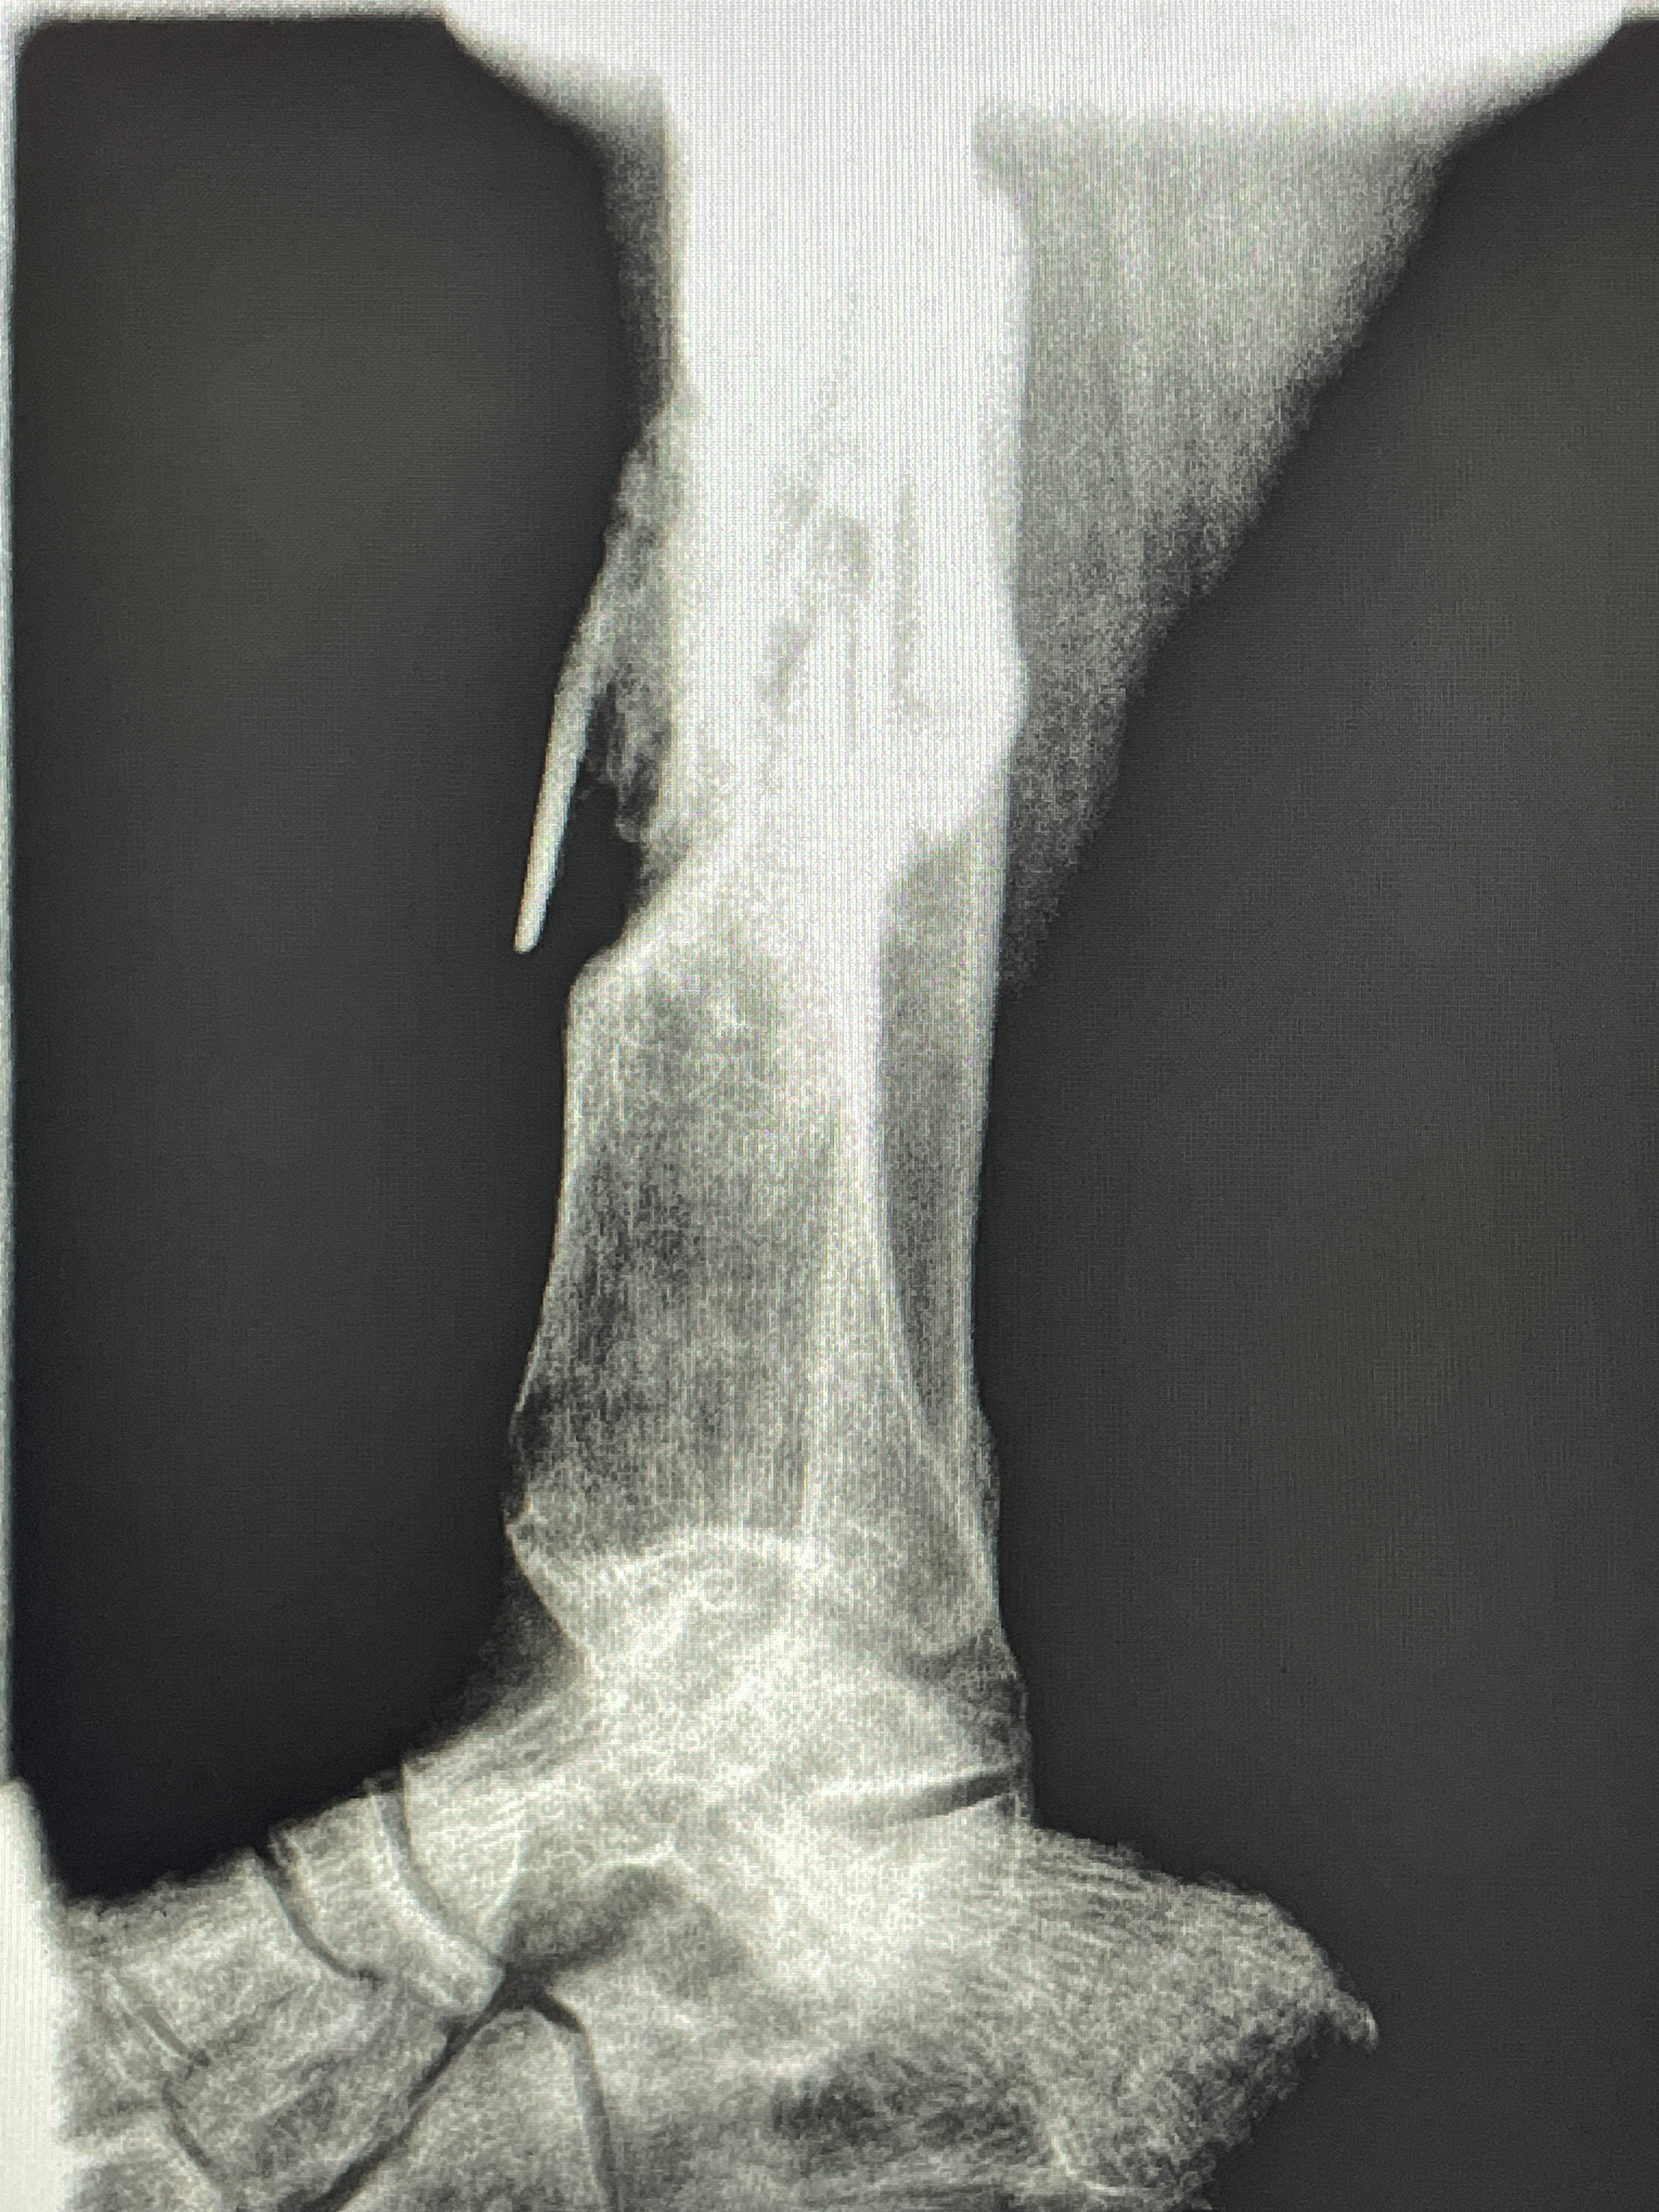

All of this happens right before he is taken back to the OR for me to do a sequestrectomy. That is to remove the dead piece of bone sticking out. I go over to the ER where the X-ray machine is. I start the computer and look up the X-rays. A few of you helped me get that X-ray machine a number of years ago. What a blessing it has been here. Thank you! The X-rays show a healed fracture. With the bones somewhat aligned. And a piece sticking out from the rest of the bone- the sequestrum.